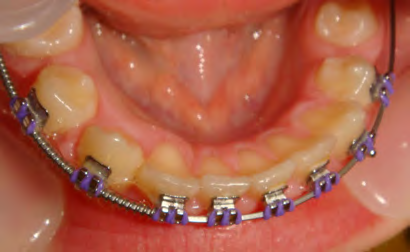

All of the patients below had been told they required extractions by orthodontists, some insisting that they could not be treated without extractions.

They were all treated without extractions, head gear or facemasks at Vakresmil and represent just a small sample of cases treated between 2004–2014.

Below are cases treated at Vakresmil without extractions within the last three years. The families had been told, “It is simply not possible for your child to be treated without extractions” by orthodontists. Judge for yourself if that was right or wrong.